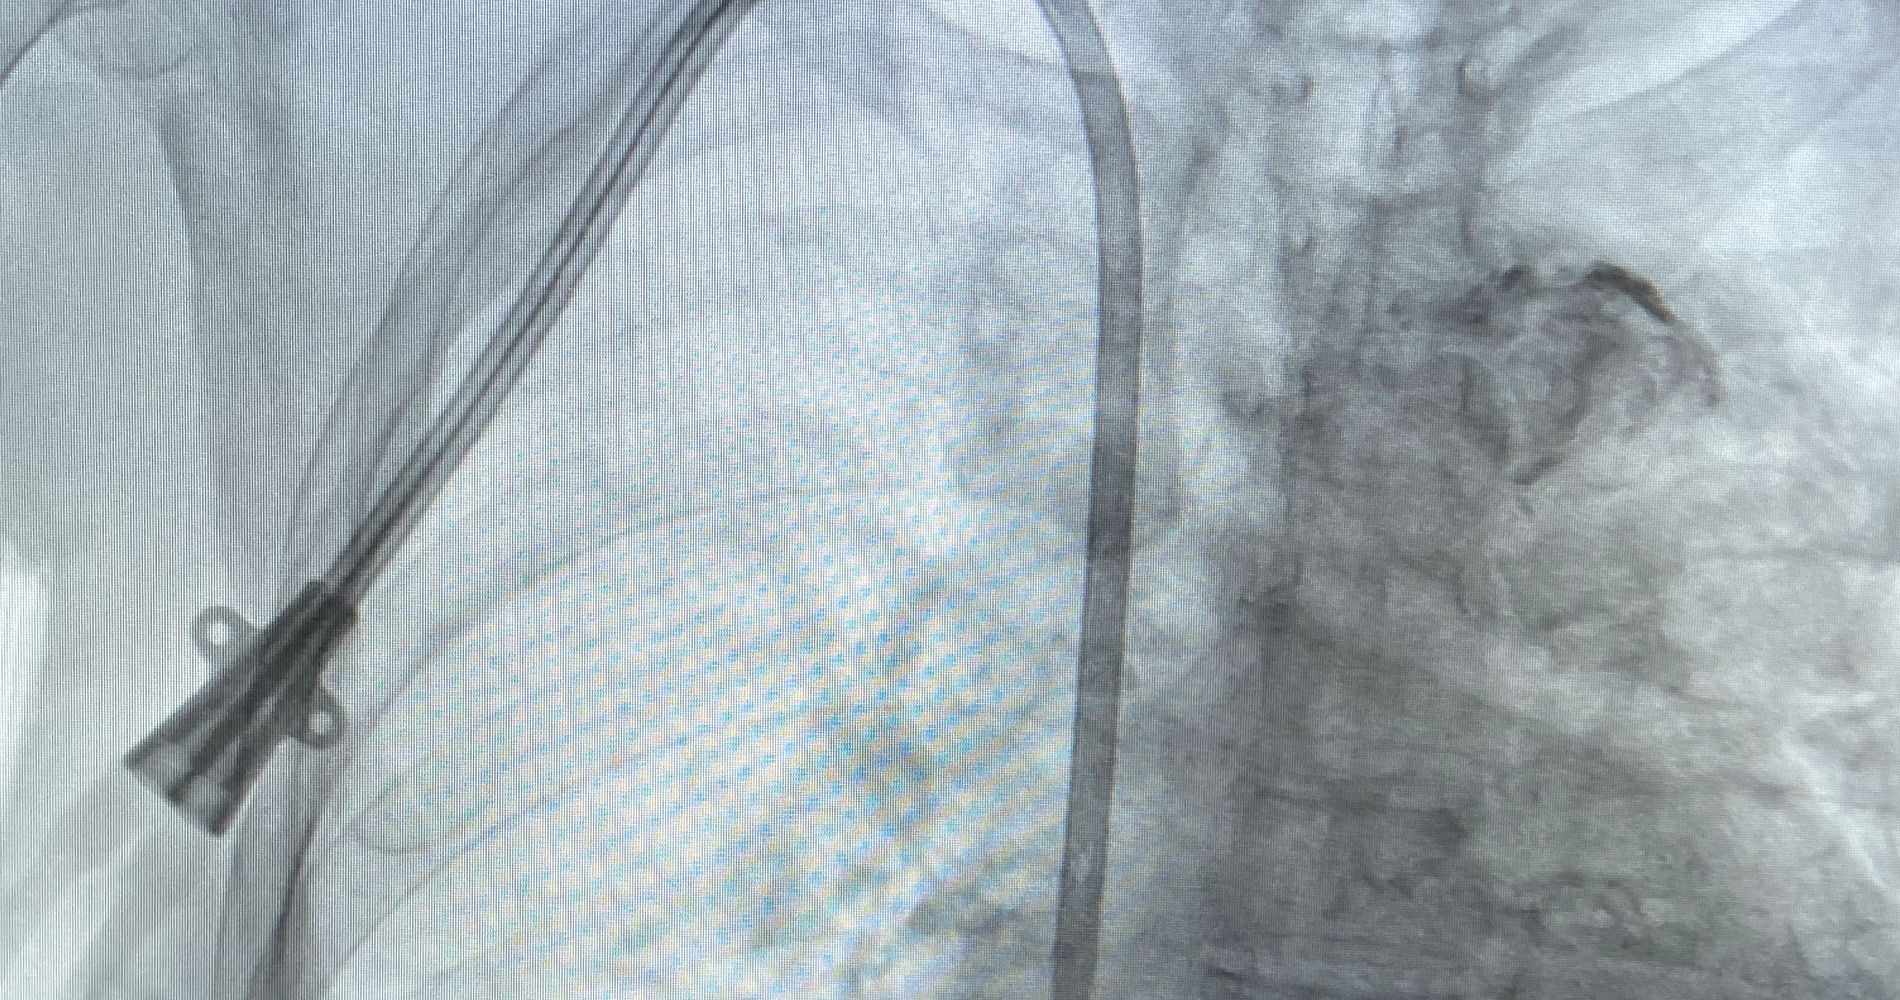

Recanalización de fístulas de diálisis disfuncionales.

Recuperación de fístulas arterio/venosas.